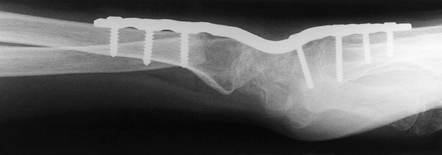

other than rheumatoid arthritis, we prefer to use the AO method of

plate fixation popularized by Hastings (39) and others (81) (Fig. 72.12 and Fig. 72.13).

Figure 72.12. Radiocarpal arthrodesis using wrist fusion plate, AP view.

Figure 72.13. Radiocarpal arthrodesis using wrist fusion plate, lateral view.